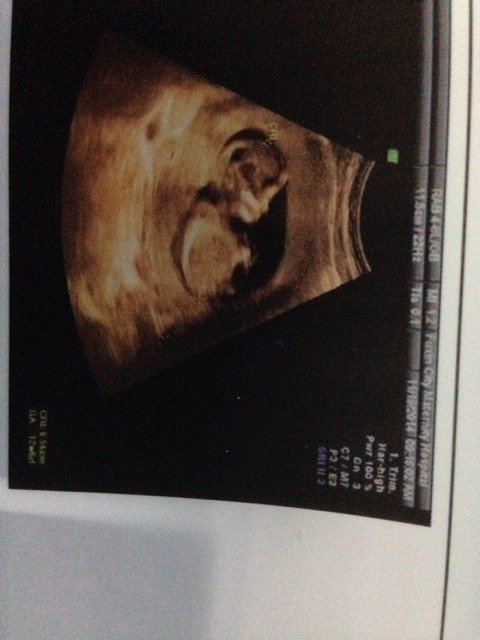

大家帮我看看宝宝这时候能看出长相嘴唇是健康吗?今天一个实习医生拿着我的片子说你看她这个12周这个是

大家帮我看看宝宝这时候能看出长相嘴唇是健康吗?今天一个实习医生拿着我的片子说你看她这个12周这个是不是那什么啊,然后医生说不是,看着不大,我问医生说什么,他俩又说没事,弄的心里好不舒服,怕哪里不健康。

你好,不要太紧张,超声检查时如果嘴唇有异常,一般情况医生会告诉你的,建议下次孕检时在照一下。